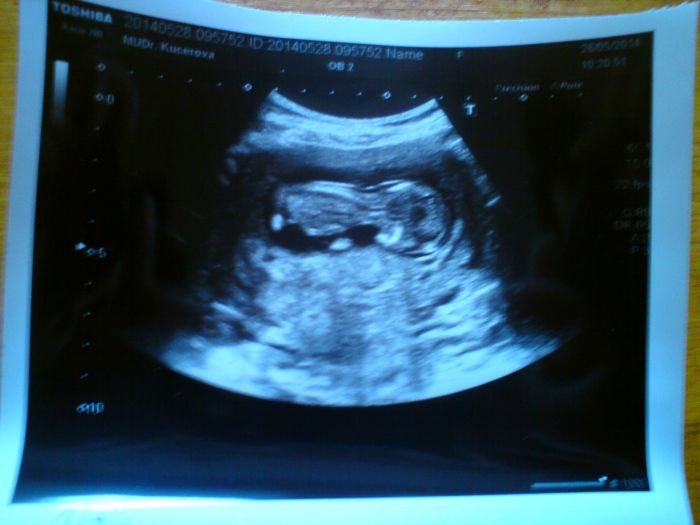

Ahoj holky moje tak včera jsem byla u dr a miminko se tam vrtí a kope a je zdravé

já měla takovou radost že je vše v pořádku i výsledky dopadly dobře...na další kontrolu jdu 18.6. a udělá mi další odběry a ty když dopadnou dobře tak už nebudu muset na žádný testy

byla tam se mnou jedna co má termín 16.6. jak jsem měla mít i já.....taky prodělala to co my...je jí 38let...no a jinak jsem byla včera podle měření miminka 12+6 a zítra začínám 14-tý týden....termín podle UZ mám 4.12....a tady je fotka mojí prdelky malinký